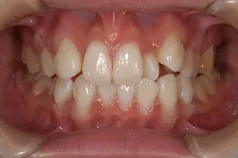

[症例]

矯正治療を行っています。

治療前は上下の歯が反対になっている所もあり、上の歯の真ん中から2本目の歯は矮小歯と言って、平均より小さな歯のため上唇が引っ込んで見えます。

インビザラインでマウスピース矯正後、オフィスホワイトニングを行い、矮小歯はラミネートベニアで修復しました。

綺麗な歯並びになるとともに、上顎の歯列のアーチが広がって、上唇がやや前方に出ることで自然な口元になりました。

- 治療期間: 1年6ヶ月

- 治療回数: 10回

- 費用: 120万円

- デメリット:治療後に矯正の後戻り防止のためのマウスピースを使用しなければならない